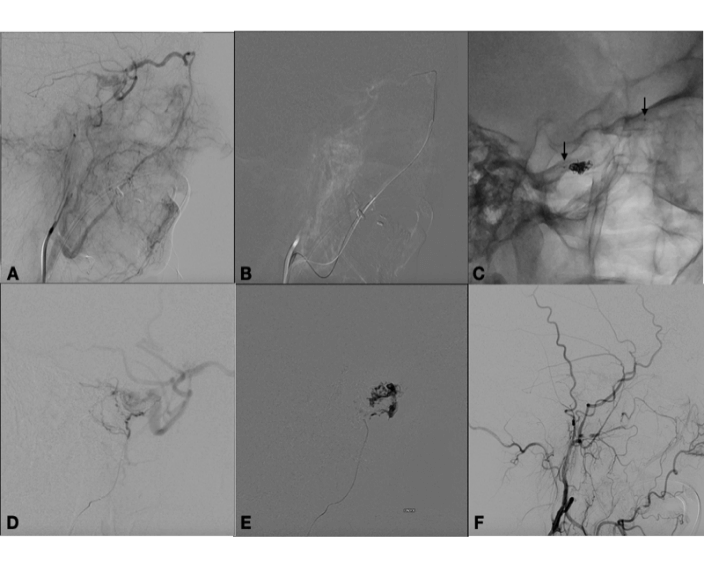

Indeed, diagnostic angiography showed a DAVF of the right cavernous sinus, fed by branches of the right external carotid artery, with drainage to the ipsilateral cavernous sinus and backflow into the superficial middle cerebral vein (Figure 1). Treatment was indicated because of the retrograde flow into the middle cerebral vein, which poses a risk of cerebral haemorrhage. Two weeks after diagnostic angiography, the patient was admitted for treatment. A repeat angiogram showed a change in the fistula pattern, with anterior venous drainage to the superior ophthalmic vein and facial vein. The decision was made to catheterize the fistula via this route and attempt coil and Histoacryl® embolization. Two micro catheters were navigated until de "foot" of the vein, one Magic 1.2 (Balt Extrusion, Montmorency, France), for the glue injection and and one excelsior SL 10 (Stryker Neurovascular, Fremont, California, USA), for coils deployment. First the coils were placed to reduce the flow inside the ophthalmic vein, and after glue was injected. Control angiography showed only partial occlusion of the fistula. The fistula was again catheterized selectively, via the middle meningeal artery, with a sonic microcatheter (Balt Extrusion, Montmorency, France) and an injection of Onyx® liquid embolic system was administered, with complete obliteration of the fistula (Figure 2). Postoperatively, the patient reported right-sided eye pain and slight proptosis. Dexamethasone 4 mg q6h was prescribed, and symptoms had resolved completely by the fourth postoperative day. The patient was asymptomatic on discharge. At 3-month follow-up, she remained free of symptoms and no longer required analgesia.

Figure 2: A) Angiography in the venous phase after injection in the external carotid artery showing drainage to the superior ophthalmic vein and facial vein. B) Catheterization of fistula through the facial vein. C) Cast of coils at the take-off of the superior ophthalmic vein and markers of the microcatheter ready for glue injection - arrows. D) Angiography in the lateral view showing microcatheter positioned in the right middle meningeal artery after partial embolization through the superior ophthalmic vein. Note residual filling of the fistula. E) Injection of Onyx® liquid embolic system into the middle meningeal artery. F) Final control angiography showing obliteration of fistula, lateral view.